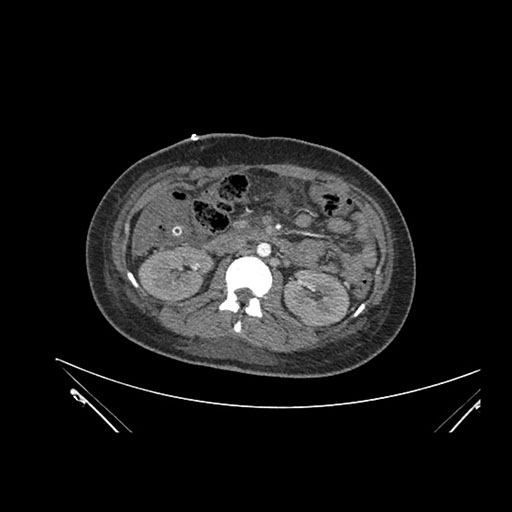

Axial Venous

Imaging analysis

Based on initial findings, which issue(s) would you be most concerned about?